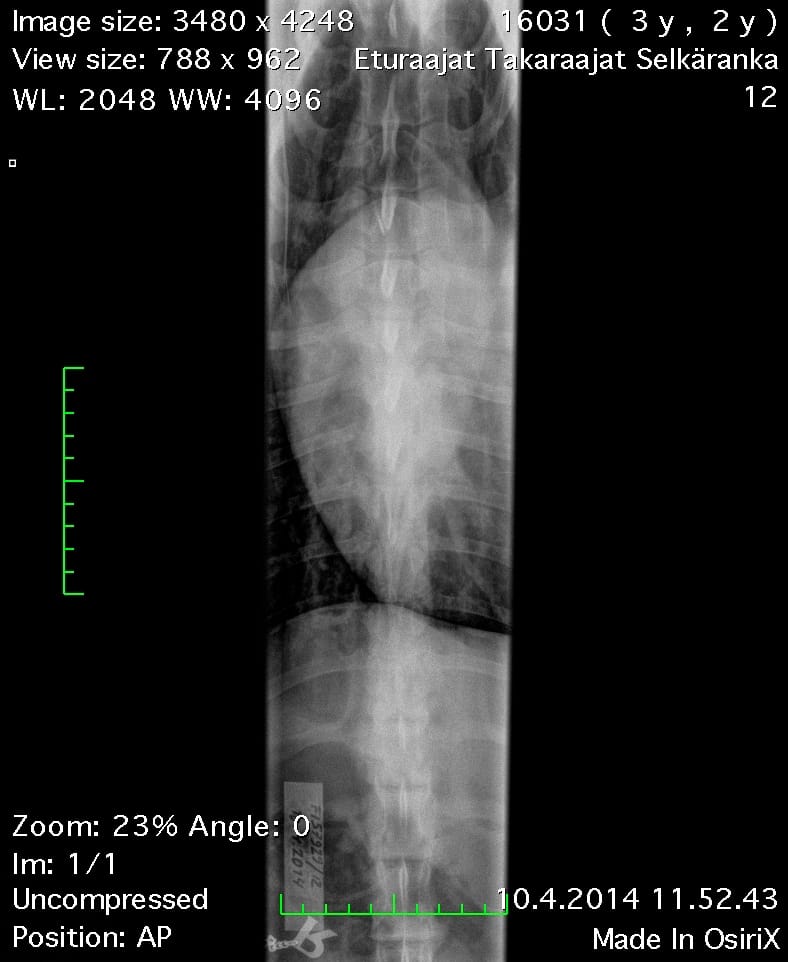

Oiva Rintaranka VD